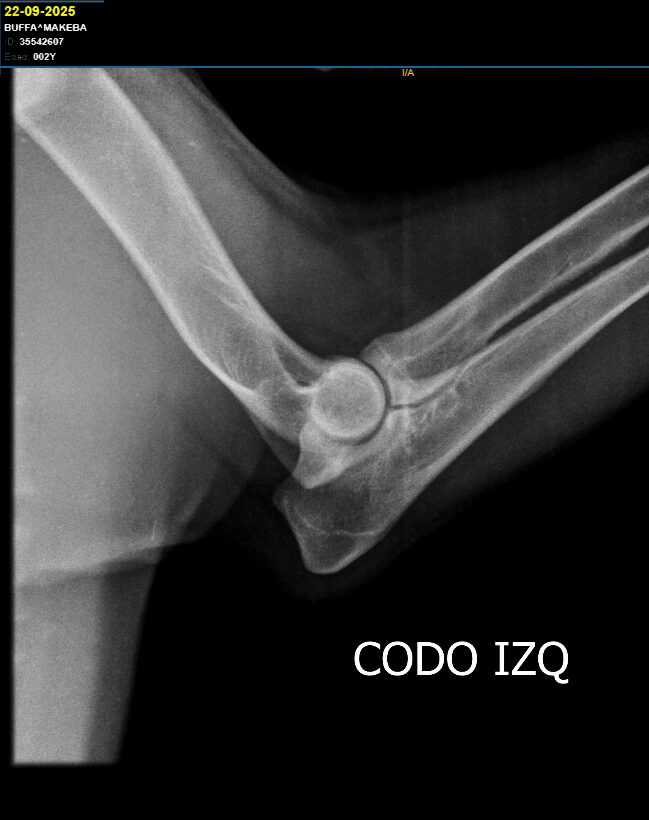

Cadera Codos:

HD A / ED 0/0